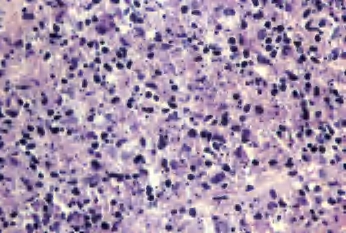

2.镜下 淋巴结结构可部分被破坏,滤泡增生,界限不清,严重时生发中心凝固性坏死呈碎片状,形成楔形坏死灶,即所谓“甜饼形”,基底直达被膜。可见大量核碎屑,无干酪样坏死和化脓性渗出,坏死边缘浆细胞增生明显。被膜内可见小淋巴细胞浸润,病变累及淋巴结的一部分或全部(图3-20、图3-21)。

图3-20 组织细胞性坏死性淋巴结炎

图3-21 组织细胞性坏死性淋巴结炎